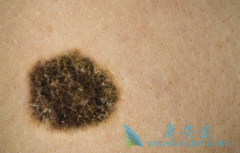

黑色素癌 患者应如何治疗?为了寻求突破,选择合适的联合治疗成为目前的研究热点。首先,基于肢端、黏膜黑色素瘤对PD-1单抗耐药机制的研究结果提示,CDK通路的变异可能介导了PD-1抑制剂的原发耐药,因此联合CDK抑制剂可能会提高PD-1抑制剂的疗效。其次 ...